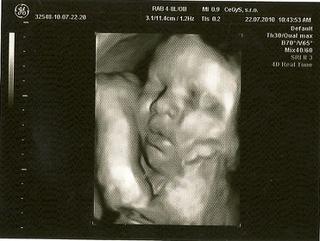

@liba78 pekna fotka vaha je myslim akurat, ja som tiez zvedava kolko bude mat buduci tyzden